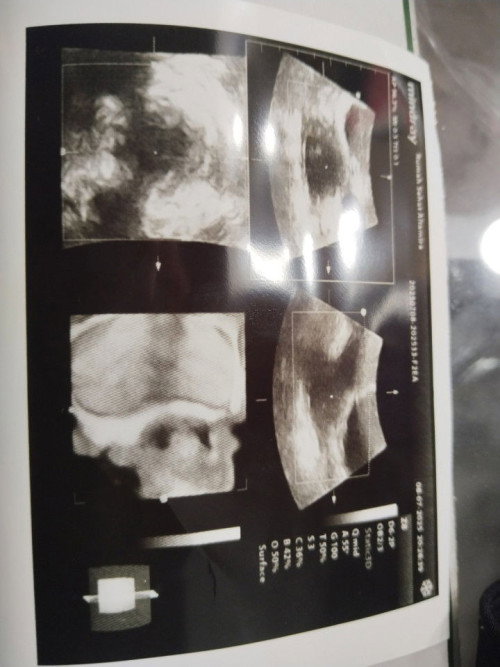

Usg kehamilan

Mohon info nya bun gimana ini hasil ny apakah bener udah ada kantung ny🙏